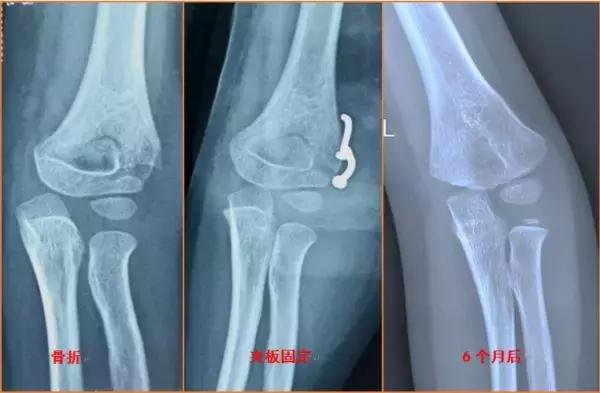

就目前流行病学研究,先天性肘内翻畸形非常罕见,80%的肘内翻都是儿童时期肱骨髁上骨折治疗不当导致,肱骨髁上骨折的远端向内侧倾斜,内侧骨质压缩嵌插,骨折外侧端张开及骨折扭转未得到有效纠正,骨折畸形愈合后导致肘内翻畸形。其他还有肱骨内髁骨折处理不当等因素导致。

儿童骨科医师推荐肘内畸形矫正最好是在骨折发生畸形愈合后半年~1年就可以治疗,过早干预可能导致骨愈合生长紊乱,骨化性肌炎等可能。有些家长或者医生会问“这个角度会不会逐渐变大的可能”,目前的研究认为绝大部分肘内翻畸形的角度一般不会随着孩子的生长发育而加重,所以畸形一旦稳定就进行矫正,手术操作简单,也不会带来以上诸多的危害。

肘内翻畸形如何纠正呢?这个时候我们需要拍摄健侧上肢的提携角,患侧肘内翻角度加上对侧上肢提携角就是我们需要矫正的角度,通过去掉一个外侧的三角形骨块就可以达到我们需要的力线和外观啦。当然更大角度的肘内翻需要不同的截骨方式或者配合尺神经松解术。